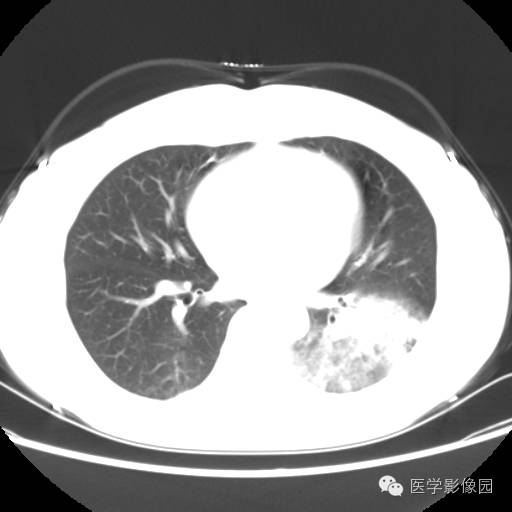

肺叶实变性支气管肺泡癌1例CT影像表现